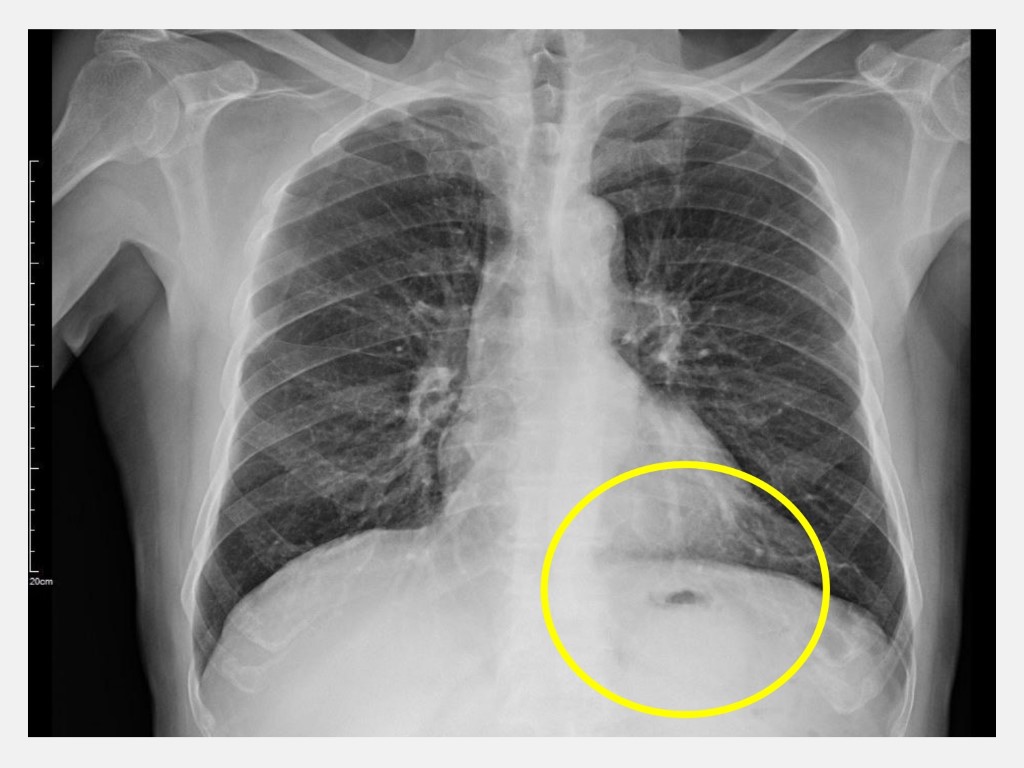

洪崇文醫師指出,肺功能檢查是診斷慢性阻塞性肺病的必要工具,許先生胸部X光檢查顯示肺部有過度充氣現象,肺功能檢查則顯示有中度肺阻塞現象。檢視許先生藥物使用的正確性,教導許先生做自主運動與呼吸訓練,如鼻子吸氣走兩步,蹶嘴吐氣走兩步或四步,中間偶爾來一次深吸、深吐,習慣後再慢慢加快步伐,提醒避免冰飲、酒及生冷水果,盡量攝取低升糖飲食,足夠蛋白質攝取量,建議每日每公斤體重攝取1.0–1.2公克蛋白質。